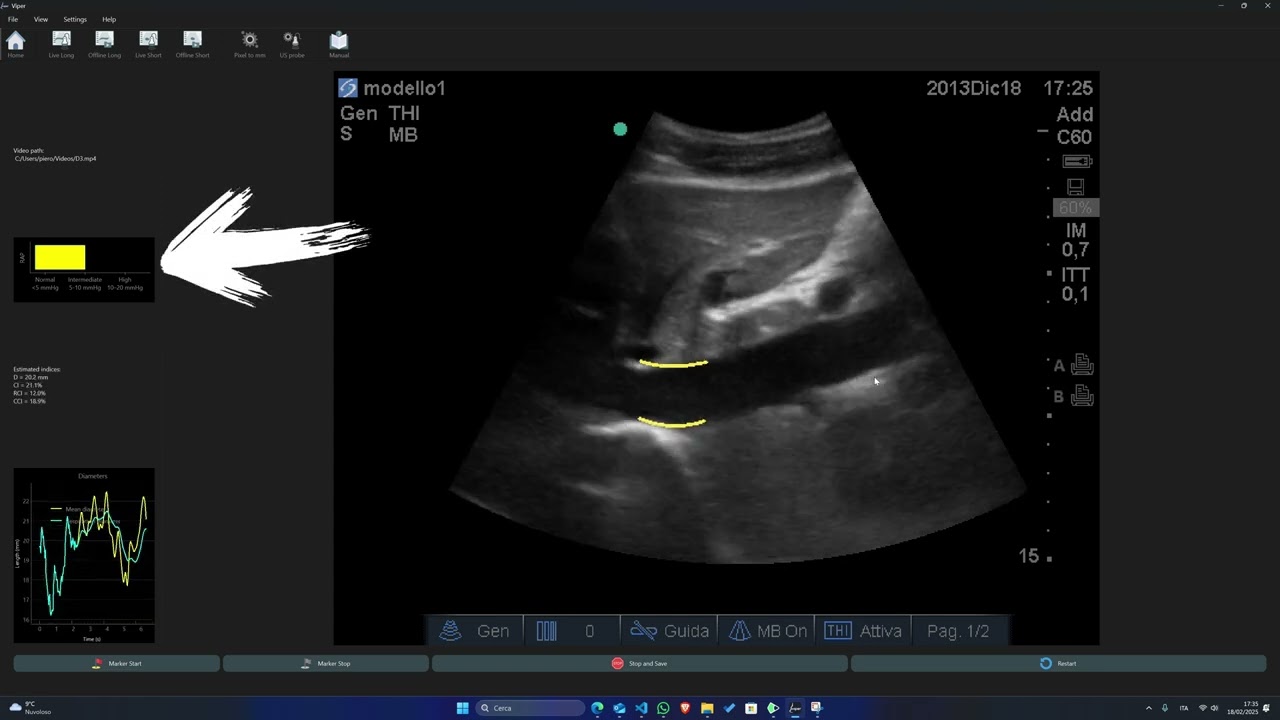

Introducing a New Indicator for Right Atrial Pressure (RAP) integrated with VIPER

Thanks to the automatic computations performed by the software, it is now possible to categorize patients into three distinct groups based on their right atrial pressure (RAP) levels: normal (0-5mmHg), intermediate (5-10mmHg), and high (10-20mmHg).